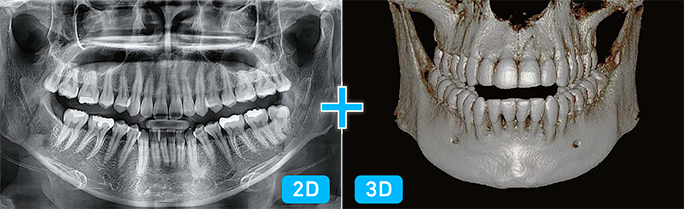

Una scansione, due immagini

Con una sola scansione, Smart Plus consente di ottenere non solo un’immagine TC, ma anche un’immagine Auto Pano. Questo significa che i pazienti che necessitano di entrambe le immagini non devono sottoporsi a due esami radiografici separati. Inoltre, le immagini TC e Auto Pano vengono visualizzate all’interno di un unico viewer, semplificando la consultazione e migliorando il flusso di lavoro.